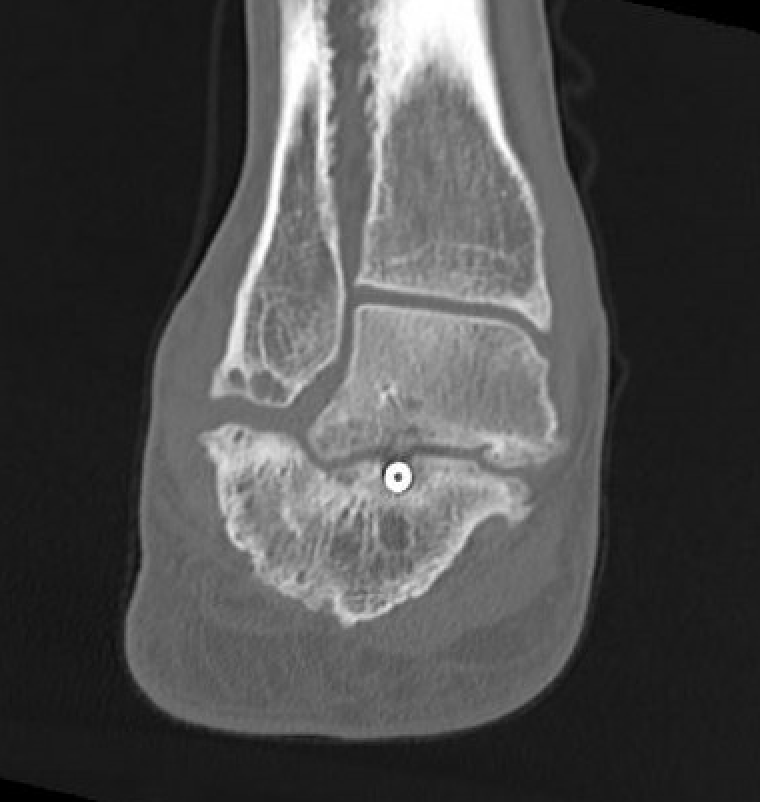

CT

Subluxation of TNJ with advanced STJ OA

TNJ OA with posterior / medial / anterior facet OA of the subtalar joint

Fixation

- 6.5 mm/ 8.0 mm cannulated screw

- inferior calcaneum into body and neck of talus / talus to calcaneum